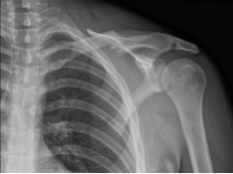

XR was presented in the office and found midshaft clavicular fracture with 1 cm overriding and moderate displacement. Midshaft Clavicle fractures are frequent traumatic injuries produced by a direct impact to the shoulder girdle, and they are most common in young, active adults.

Left Clavicle in AP position